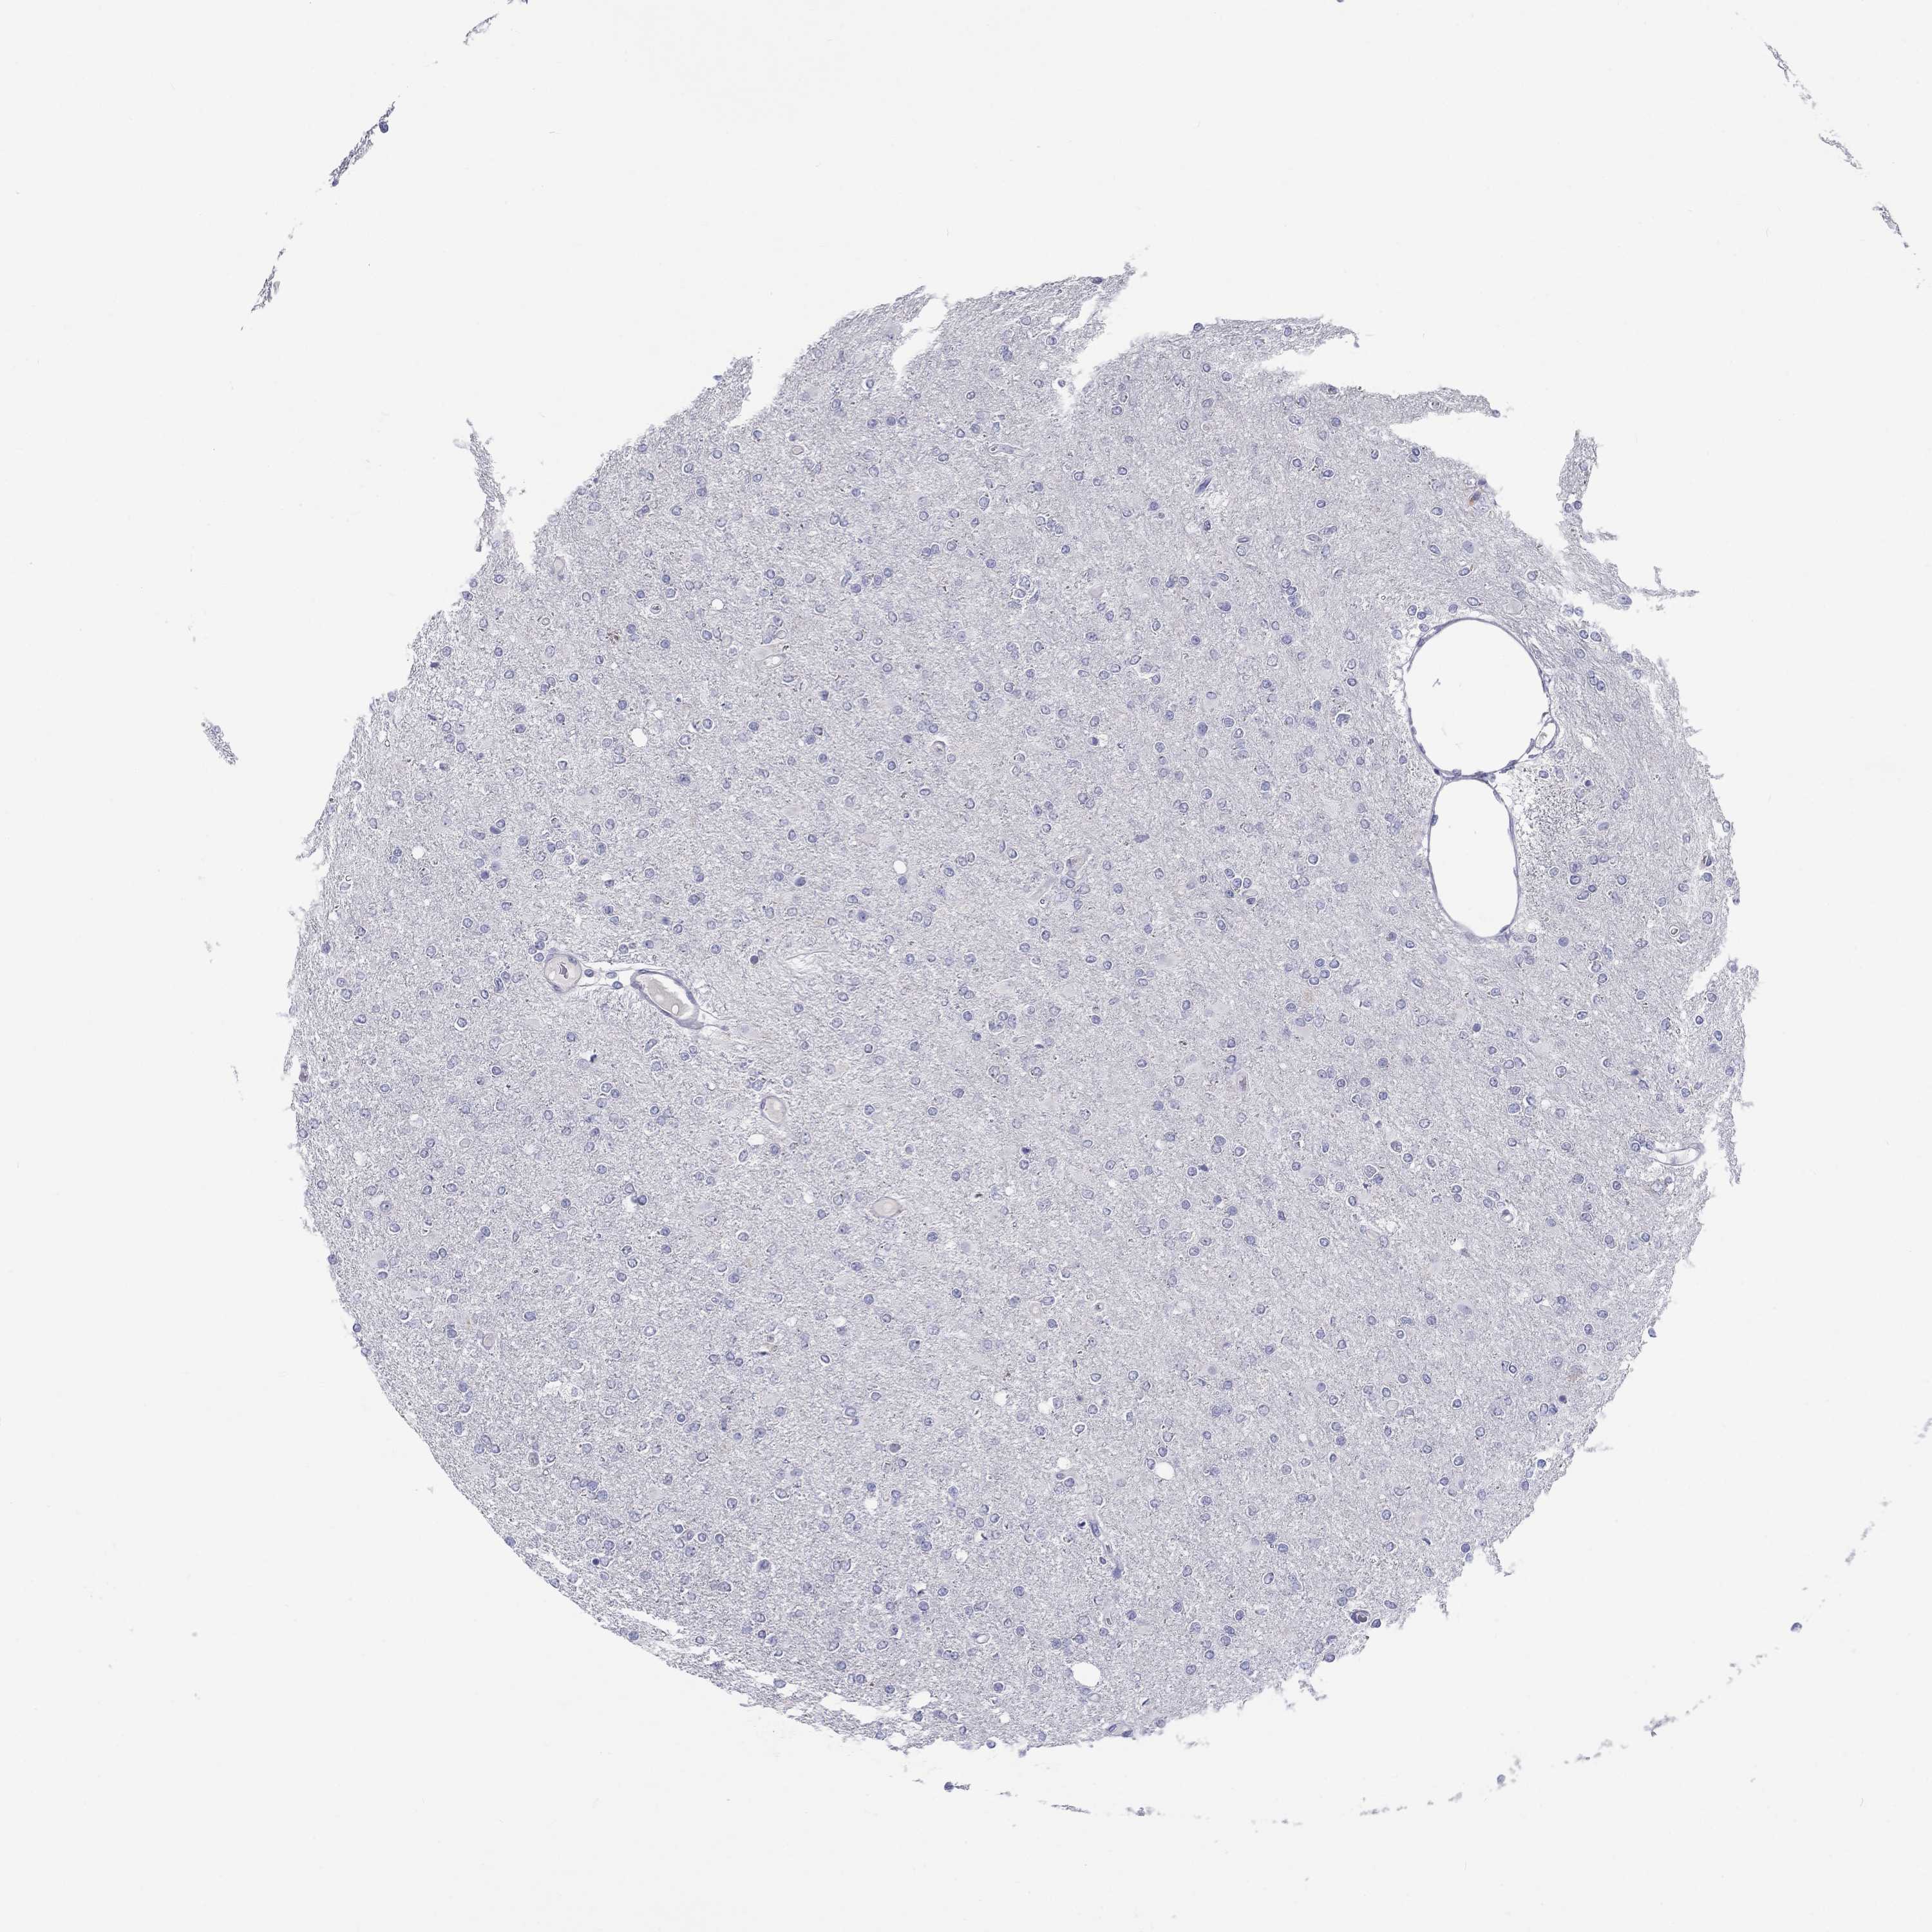

GLIOMA - Protein expressioni

A mouse-over function shows sample information and annotation data. Click on an image to view it in a full screen mode. Samples can be filtered based on level of antibody staining by selecting one or several of the following categories: high, medium, low and not detected. The assay and annotation is described here.

Note that samples used for immunohistochemistry by the Human Protein Atlas do not correspond to samples in the TCGA dataset.

Antibody stainingi

Antibody staining in the annotated cell types in the current human tissue is reported as not detected, low, medium, or high, based on conventional immunohistochemistry profiling in selected tissues. This score is based on the combination of the staining intensity and fraction of stained cells.

Each image is clickable and will lead to virtual microscopy that enables deeper exploration of all samples and also displays staining intensity scores, fraction scores and subcellular localization as well as patient and tissue information for each sample.

Antibody HPA068138

Antibody HPA071902

Glioma, malignant, Low grade

Glioma, malignant, High grade

Glioma, malignant, NOS